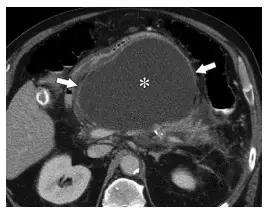

APFCs 发生于发病 4 周内,仅见于 IEP 患者。因为没有坏死物,APFCs 表现为胰周无壁均质液性密度(图 4)。

APFCs 仅见于胰周,如果胰腺实质内有相似表现的病灶为 ANC,诊断就不再是 IEP 而是坏死性胰腺炎。多数 APFCs 能够自发吸收,而且引流有继发感染的可能,所以不建议引流治疗。

图 4 合并 APFCs 的 49 岁男性 IEP 患者。a 腹痛第一天,可见肾脏左前方少量均质液性密度(箭头)。胰腺强化正常。b~d 腹痛发生后 10 天,小网膜囊(b)、胰周(c)、双侧肾前间隙(d)可见大量均质液性密度,征象和 APFCs 相符。图 c 中的箭头指正常强化的胰尾